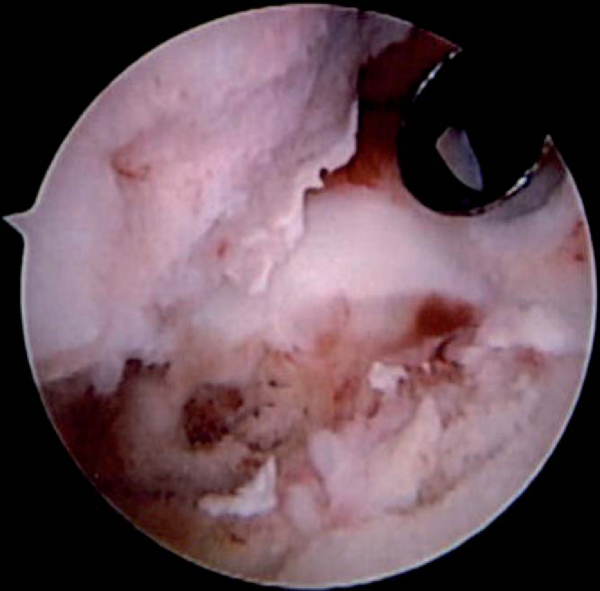

The most difficult to manage of these various lesions is chondrolysis of the glenohumeral joint. Although this has been described to follow thermal surgery, the exact cause has yet to be elucidated. Arthroscopy reveals an aggressive destruction of the entire articular surface of the humeral head and glenoid, severe synovitis and capsular damage, and almost an avascular necrosis type of destruction of the humeral head (

Fig. 7-8

). Biologic glenoid resurfacing with or without humeral head replacement seems to provide the best relief.